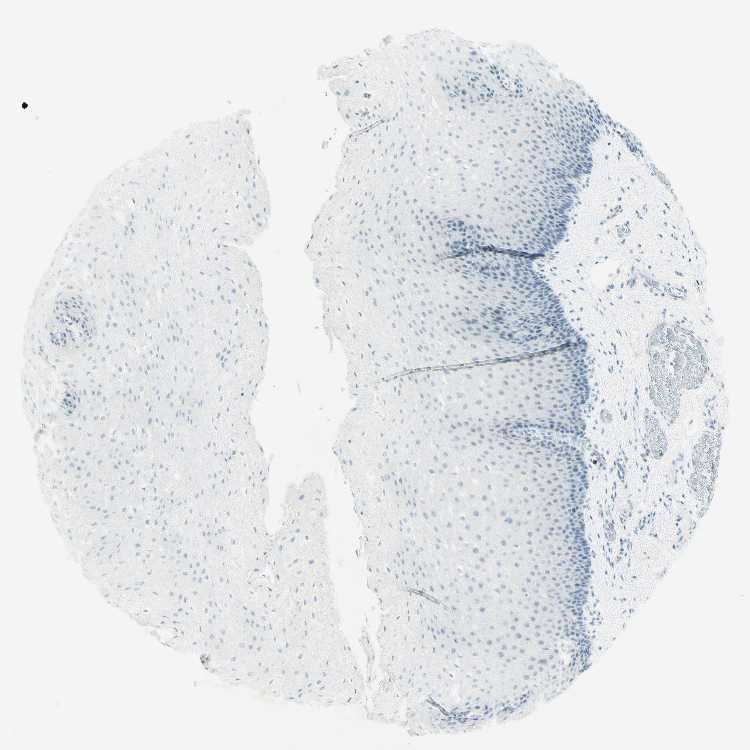

ESOPHAGUS - Antibody stainingi

Antibody staining in the annotated cell types in the current human tissue is reported as not detected, low, medium, or high, based on conventional immunohistochemistry profiling in selected tissues. This score is based on the combination of the staining intensity and fraction of stained cells.

Each image is clickable and will lead to virtual microscopy that enables deeper exploration of all samples and also displays staining intensity scores, fraction scores and subcellular localization as well as patient and tissue information for each sample.

Antibody HPA011284Antibody CAB026403

Squamous epithelial cells Not detectedNot detected